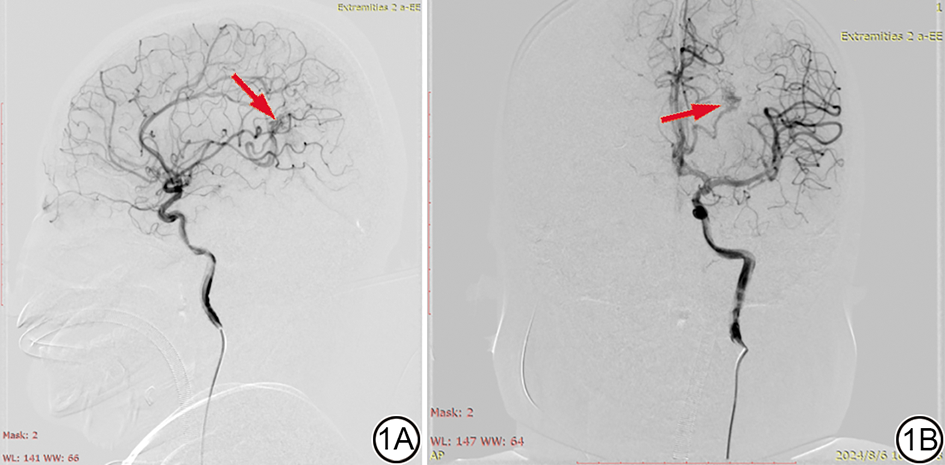

统计分析发现,不同类型的CVMs的检出情况在DSA、CTA、MRA及CTA联合MRA之间差异无统计学意义(χ2=4.626,P=0.969)。而与DSA(图1)相比,CTA、MRA单独检测检出CVMs的数量(34/38、33/38)低于DSA,差异具有统计学意义(P<0.05),而CTA与MRA联合诊断检出CVMs的数量(40/38)与DSA接近,差异无统计学意义(P>0.05)(表1)。典型病例的DSA图像、CTA图像和MRA图像分别见图1, 图2, 图3

图1  颈内动脉及左侧椎动脉的DSA图像。男,11岁,因脑出血入院,确诊为脑动静脉畸形。1A:左侧顶叶可见动静脉畸形血管(红箭);1B:供血动脉来自左侧胼周动脉,引流至左侧横窦,红色箭头为畸形血管。DSA:数字减影血管造影。

Fig. 1  DSA images of the internal carotid artery and the left vertebral artery. Male, 11 years old, admitted to the hospital due to cerebral hemorrhage and diagnosed with cerebral arteriovenous malformation. 1A: The arteriovenous malformation vessels are seen onthe left parietal lobe (red arrow). 1B: The blood supply artery originated from the left peri-capsular artery and drained into the left transverse sinus. The red arrow indicated the malformed vessel. DSA: digital subtraction angiography.